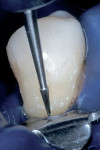

During the second appointment, the external layer of the provisional glass ionomer restoration was removed to develop an ideal Class V adhesive preparation design, while a 2-mm layer of resin-modified glass ionomer remained as the artificial dentin layer. To effect an esthetic result, a chamfer 0.3 mm in depth was placed along the occlusal margin with a long tapered diamond (#6850, Brasseler USA, Savannah, GA). A scalloped bevel was developed 0.5 mm in the enamel in order to interrupt the straight line of the chamfer (Figure 5A and Figure 5B). The bevel was placed on all margins that were in enamel to reduce the potential of microleakage. However, a butt joint would have been prepared if the gingival margin was in cementum/dentin.

The preparation was polished with rubber cups that contained a premixed slurry of pumice and 2% chlorhexidine (Consepsis). The preparation was rinsed and lightly air-dried. A two-component self-etch system (UniFil® Bond, GC America) was used. The self-etching primer was applied to the preparation and allowed to set for 20 seconds, dried gently for 5 seconds, and the bonding agent was applied to the enamel and dentin surfaces and light-cured for 10 seconds (Figure 6A, Figure 6B, Figure 6C).